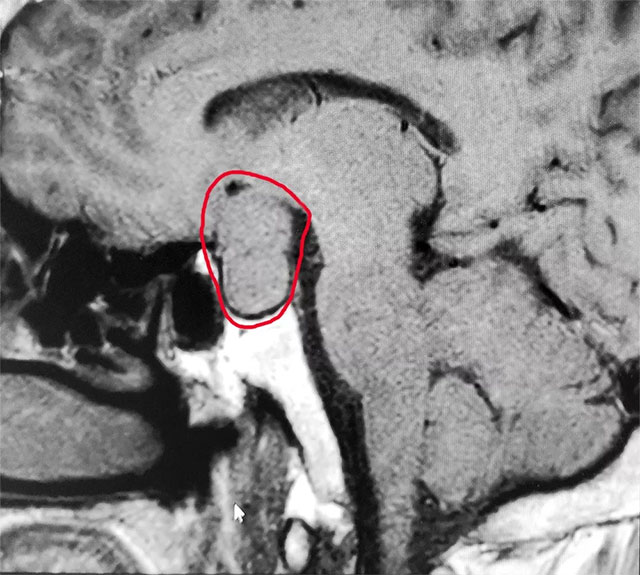

▲ 術(shù)前MR影像:垂體大腺瘤,超蝶鞍生長(zhǎng)

針對(duì)患者情況,6B病區(qū)主任潘仁龍基于多年臨床經(jīng)驗(yàn)立即作出判斷,急行頭顱鞍區(qū)MRI平掃+增強(qiáng),顯示:蝶鞍擴(kuò)大,鞍底骨質(zhì)下陷;鞍內(nèi)垂體上緣膨隆,腺垂體中央見(jiàn)一枚類(lèi)橢圓形異常信號(hào),大小約2.8*1.9cm;T1WI上呈等信號(hào)、T2WI呈等信號(hào)為主局部見(jiàn)斑片狀低信號(hào),輪廓光整,增強(qiáng)后可見(jiàn)大部分明顯強(qiáng)化,視交叉可見(jiàn)上抬?紤]為垂體腺瘤伴局部卒中。

潘仁龍主任指出,CT在垂體卒中急性期平掃時(shí)即可見(jiàn)瘤內(nèi)的高密度影出血灶,很容易辨別,但當(dāng)進(jìn)入亞急性期后則呈等密度,難于鑒別。因此,在高度懷疑垂體卒中的病例中應(yīng)首選MRI掃描。此外,MRI 還能提供較 CT 更為清晰的三維空間解剖結(jié)構(gòu),它對(duì)腫瘤以及瘤體與周邊正常組織的關(guān)系都可起到良好的顯示作用。因此MRI是垂體瘤卒中的首選影像學(xué)檢查手段,而在急性期,尤其是超急性期則首選CT。